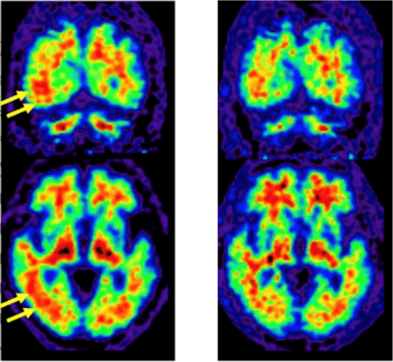

左:従来PEF/CT装置により得られた脳アミロイドPET画像

黄色矢印の部分で灰白質にアミロイドの分布を示すPET薬剤集積がひろがっているようにみえ(赤い部分が脳の表面までひろがっている)、同部にアミロイドが蓄積していると判定された。

右:本装置により得られた脳アミロイドPET画像

従来PET/CT装置でアミロイド蓄積陽性と判定された部分について、灰白質まで集積が及んでいないことが明白である(赤い部分は脳の表面まで達していない)。